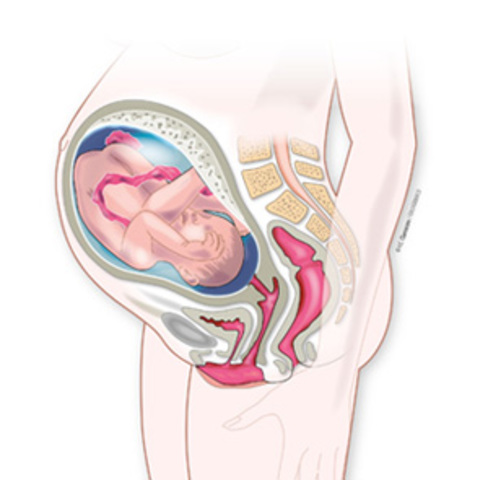

al bebé le cuesta moverse y estirarse dentro del útero cada vez más porque su crecimiento se acelera. Si no ha acomodado todavía su cabeza hacia abajo, lo hará cerca de esta semana. . Su actividad y su rápido crecimiento continúan en todos los aspectos. Sin ir más lejos, cada día tu bebé elimina aproximadamente medio litro de orina al líquido amniótico.

• SEMANA 32

SEMANA 32

El bebé pesa 1.800 gramos y mide unos 42 centímetros de pies a cabeza en la semana 32 de embarazo.

Todavía el diámetro de la cabeza sigue siendo mayor que el del abdomen, pero el aspecto del feto ya se parece bastante al de un recién nacido.